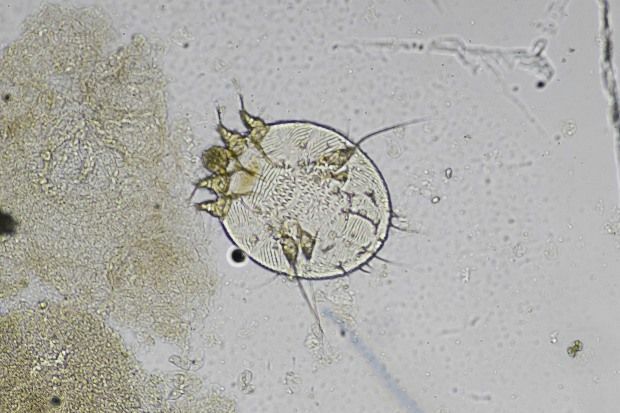

Scabies: symptoms and eradication